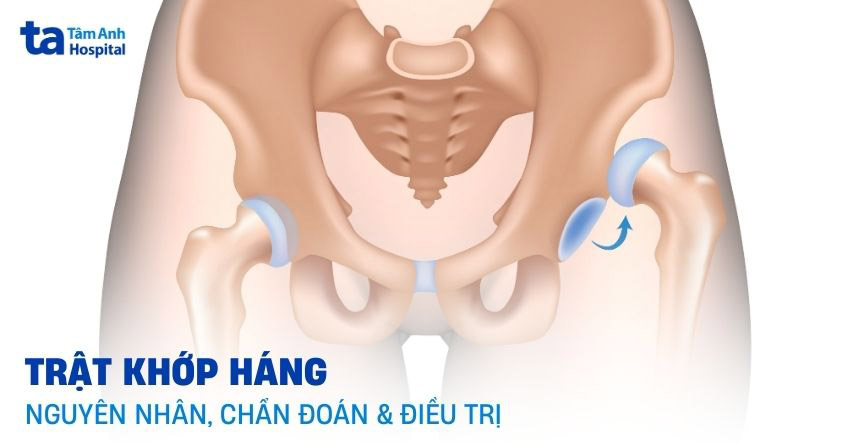

Khớp háng được tạo bởi chỏm của xương đùi khớp với ổ cối của xương chậu và bao xung quanh bởi bao khớp háng.

Trật khớp háng là tình trạng chỏm xương đùi bị trật ra khỏi ổ cối, thường xảy ra do chấn thương. Đây là một trường hợp cấp cứu y tế, gây đau cấp tính dữ dội, làm tê liệt chân cho đến khi được nắn trật.

Dưới đây là một số kiểu trật khớp háng, thường gặp nhất phân loại theo giải phẫu: (2)

Khớp háng trật ra sau chiếm đến 90% trong tổng số các trường hợp. Tình trạng này xảy ra khi tải trọng dồn trục lên xương đùi, đặc biệt là khi thực hiện động tác gập và khép khớp háng. Khớp háng là một khớp lớn, lực trật được khớp thường phải mạnh, cơ chế chấn thương năng lượng cao, nên trật khớp háng thường đi kèm với các tổn thương xương kế cận như gãy ổ bờ sau ổ cối, gãy chỏm xương đùi, chấn thương dây thần kinh tọa và chấn thương đầu gối cùng bên (lên đến 25%).

Trật khớp háng ra phía trước hiếm gặp hơn (10%), xảy ra ở tư thế chân dạng và xoay hông ra ngoài. Trên lâm sàng, bệnh nhân thường đến bệnh viện ở tư thế khớp háng duỗi và xoay ngoài.